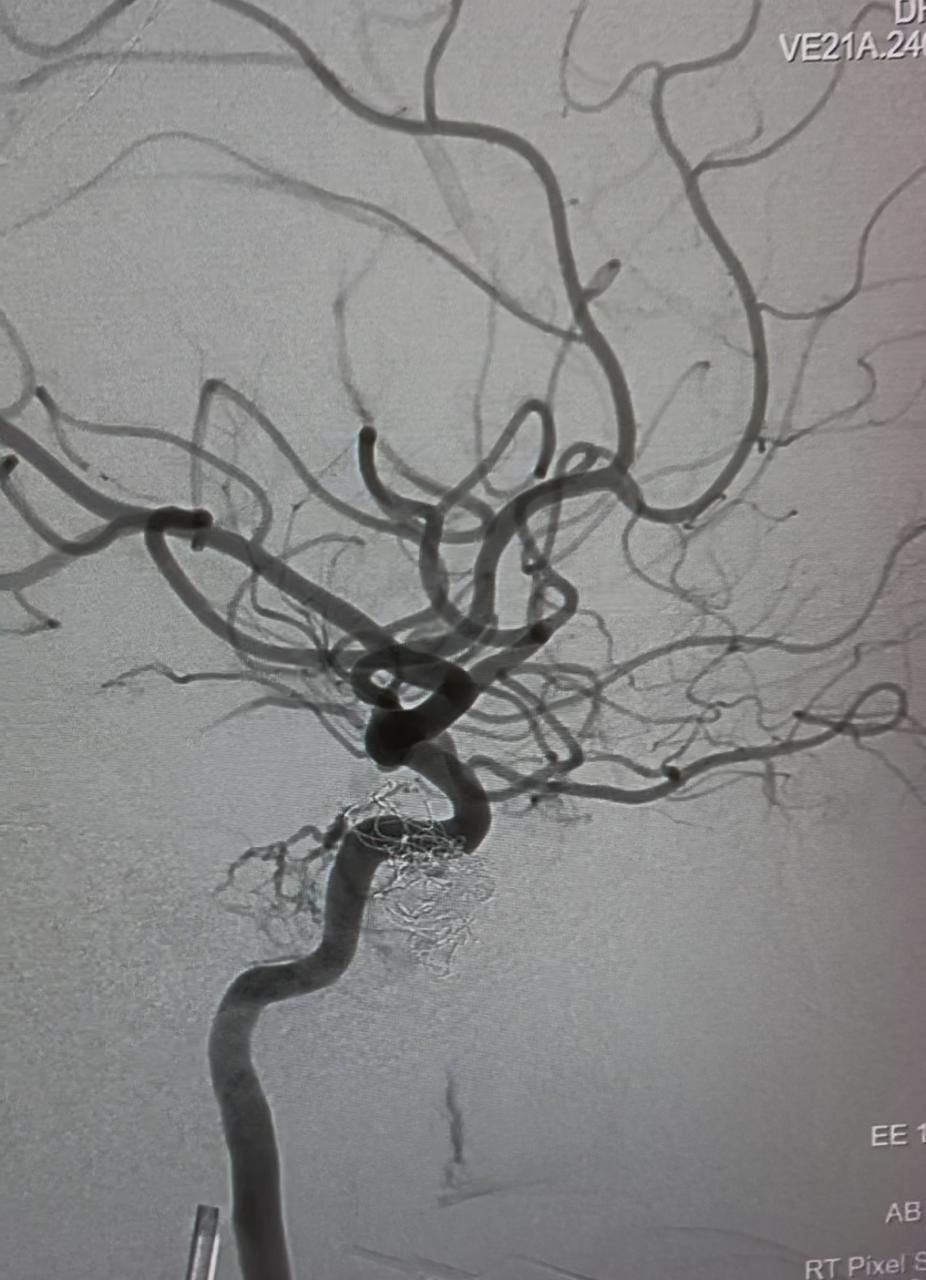

نجح فريقٌ طبيٌّ متخصصٌ من مستشفى خولة في إجراء تدخلٍ عاجلٍ بمستشفى صحار لعلاج حالةٍ معقّدةٍ لمريضٍ كان يُعاني من تشابكٍ غير طبيعي بين الشرايين والأوردة الدماغية، وذلك باستخدام تقنية القسطرة العصبية المتقدمة.

وتعود تفاصيل الحالة إلى استقبال المريض في مستشفى صحار بعد معاناته من أعراض عصبية متكررة استدعت إجراء فحوصات دقيقة، حيث أظهرت النتائج الأولية وجود تشوه وعائي دماغي معقد يُعدُّ من الحالات النادرة والحساسة التي تتطلب تدخلاً تخصُّصياً عالي الدقة وعلى ضوء ذلك، جرى التنسيق المباشر مع مستشفى خولة، كونه مركزاً مرجعياً متخصّصاً في مثل هذه التدخلات، لوضع خطة علاجية مشتركة تضمن أفضل النتائج للمريض.

وأُجريت العملية باستخدام القسطرة العصبية في مستشفى صحار، وهي تقنية علاجية دقيقة تُنفذ عبر الأوعية الدموية دون الحاجة إلى تدخل جراحي تقليدي، ما يُسهم في تقليل المخاطر وتسريع فترة التعافي وقد تكلّلت العملية بالنجاح، وتمكّن الفريق الطبي من علاج التشابك الوعائي بكفاءة عالية، مع تحسُّن ملحوظ في الحالة الصحية للمريض.